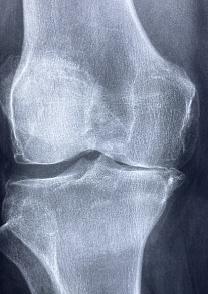

무릎 관절에 좋은 운동 및 무릎 관절에 관한 정보를 알아보도록 하겠습니다. 무릎 관절 통증은 많은 사람들이 겪는 공통된 건강 문제입니다. 무릎 관절은 우리 몸의 무게를 지탱하고, 걷거나 달리거나 앉거나 일어서는 등 다양한 움직임에 참여하는 중요한 부위이기 때문에, 무릎 관절에 힘이 가해지거나 손상되면 통증이 발생할 수 있습니다.

1. 연골 손상: 연골은 뼈와 뼈 사이에 있는 부드러운 조직으로, 뼈가 서로 마찰하지 않도록 보호하고 충격을 흡수하는 역할을 합니다. 연골이 손상되면 뼈가 서로 부딪치면서 통증이 발생하고, 관절의 움직임이 제한될 수 있습니다. 연골 손상의 원인은 나이가 들면서 자연적으로 연골이 닳거나, 스포츠나 사고 등으로 인한 외부적인 충격이 있을 수 있습니다.

4. 관절염: 관절염은 관절에 염증이 생기는 질환을 말합니다. 관절염에는 여러 종류가 있지만, 가장 흔한 것은 골관절염과 류마티스 관절염입니다. 골관절염은 나이가 들면서 연골이 닳아서 발생하는 질환으로, 주로 50세 이상의 사람들에게 많이 나타납니다. 류마티스 관절염은 면역 체계가 잘못 작동하여 자신의 조직을 공격하는 자가면역 질환으로, 주로 40세 이하의 여성에게 많이 나타납니다. 관절염이 발생하면 무릎 관절에 통증, 부기, 열감, 강직감 등의 증상이 나타날 수 있습니다.

무릎 관절의 원인은 다양합니다. 가장 흔한 원인은 연령에 따른 자연적인 퇴행입니다. 나이가 들면서 연골이 닳아가고 관절의 윤활액이 감소하면서 무릎 관절에 마찰이 발생하고 통증이 생깁니다. 이를 노화성 관절염이라고 합니다. 노화성 관절염은 만성적이고 진행적인 질환으로 완치하기 어렵습니다. 하지만 적절한 치료와 운동으로 증상을 완화하고 진행을 늦출 수 있습니다.